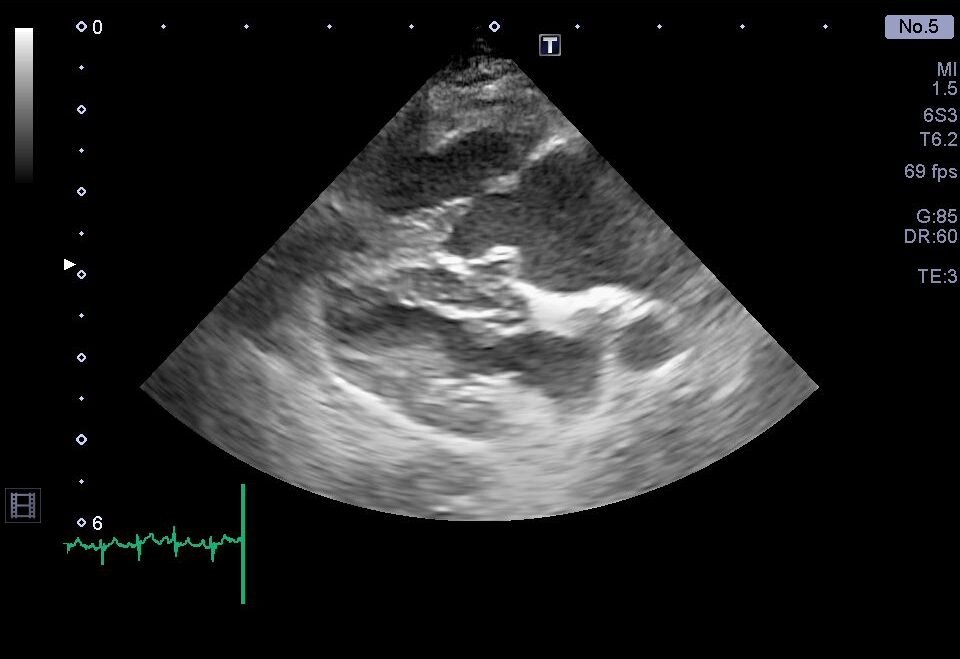

治療強化後の心臓超音波検査。右心系拡大の改善を認める。

心室中隔扁平化の改善

以前と比較して、三尖弁逆流速度の低下を認める

肺高血圧症に対する治療強化後の再診察では、上記のような心臓形態の改善を認めた他、呼吸の改善や腹水の顕著な減少を認めました。

これらの結果から、シルデナフィルの増量と利尿剤の追加が奏功したと判断し、内服薬による継続治療を行いました。